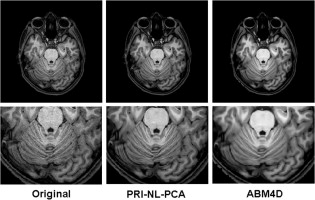

In this page we present a novel method for MRI denoising that exploits both the sparseness and self-similarity properties of the MR images. The proposed method is a two-stage approach that first filters the noisy image using a non local PCA thresholding strategy by automatically estimating the local noise level present in the image and second uses this filtered image as a guide image within a rotationally invariant non-local means filter. The proposed method internally estimates the amount of local noise presents in the images that enables applying it automatically to images with spatially varying noise levels and also corrects the Rician noise induced bias locally. The proposed approach has been compared with related state-of-the-art methods showing competitive results in all the studied cases..

Manjón J.V., Coupe P., Buades A. MRI Noise Estimation and Denoising Using Non-Local PCA. Medical Image Analysis, 22:35-47. 2015.